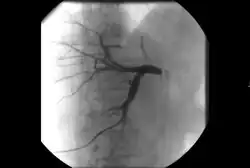

• Angiography: Imaging the blood vessels to look for abnormalities with the use of various contrast media, including iodinated contrast, gadolinium based agents, and CO2 gas.[3]

Biliary stenosis

Biliary intervention[12]

• Placement of catheters in the biliary system to bypass biliary obstructions and decompress the biliary system.

• Placement of permanent indwelling biliary stents.

• Cholecystostomy: Placement of a tube into the gallbladder to remove infected bile in patients with cholecystitis, an inflammation of the gallbladder, who are too frail or too sick to undergo surgery.